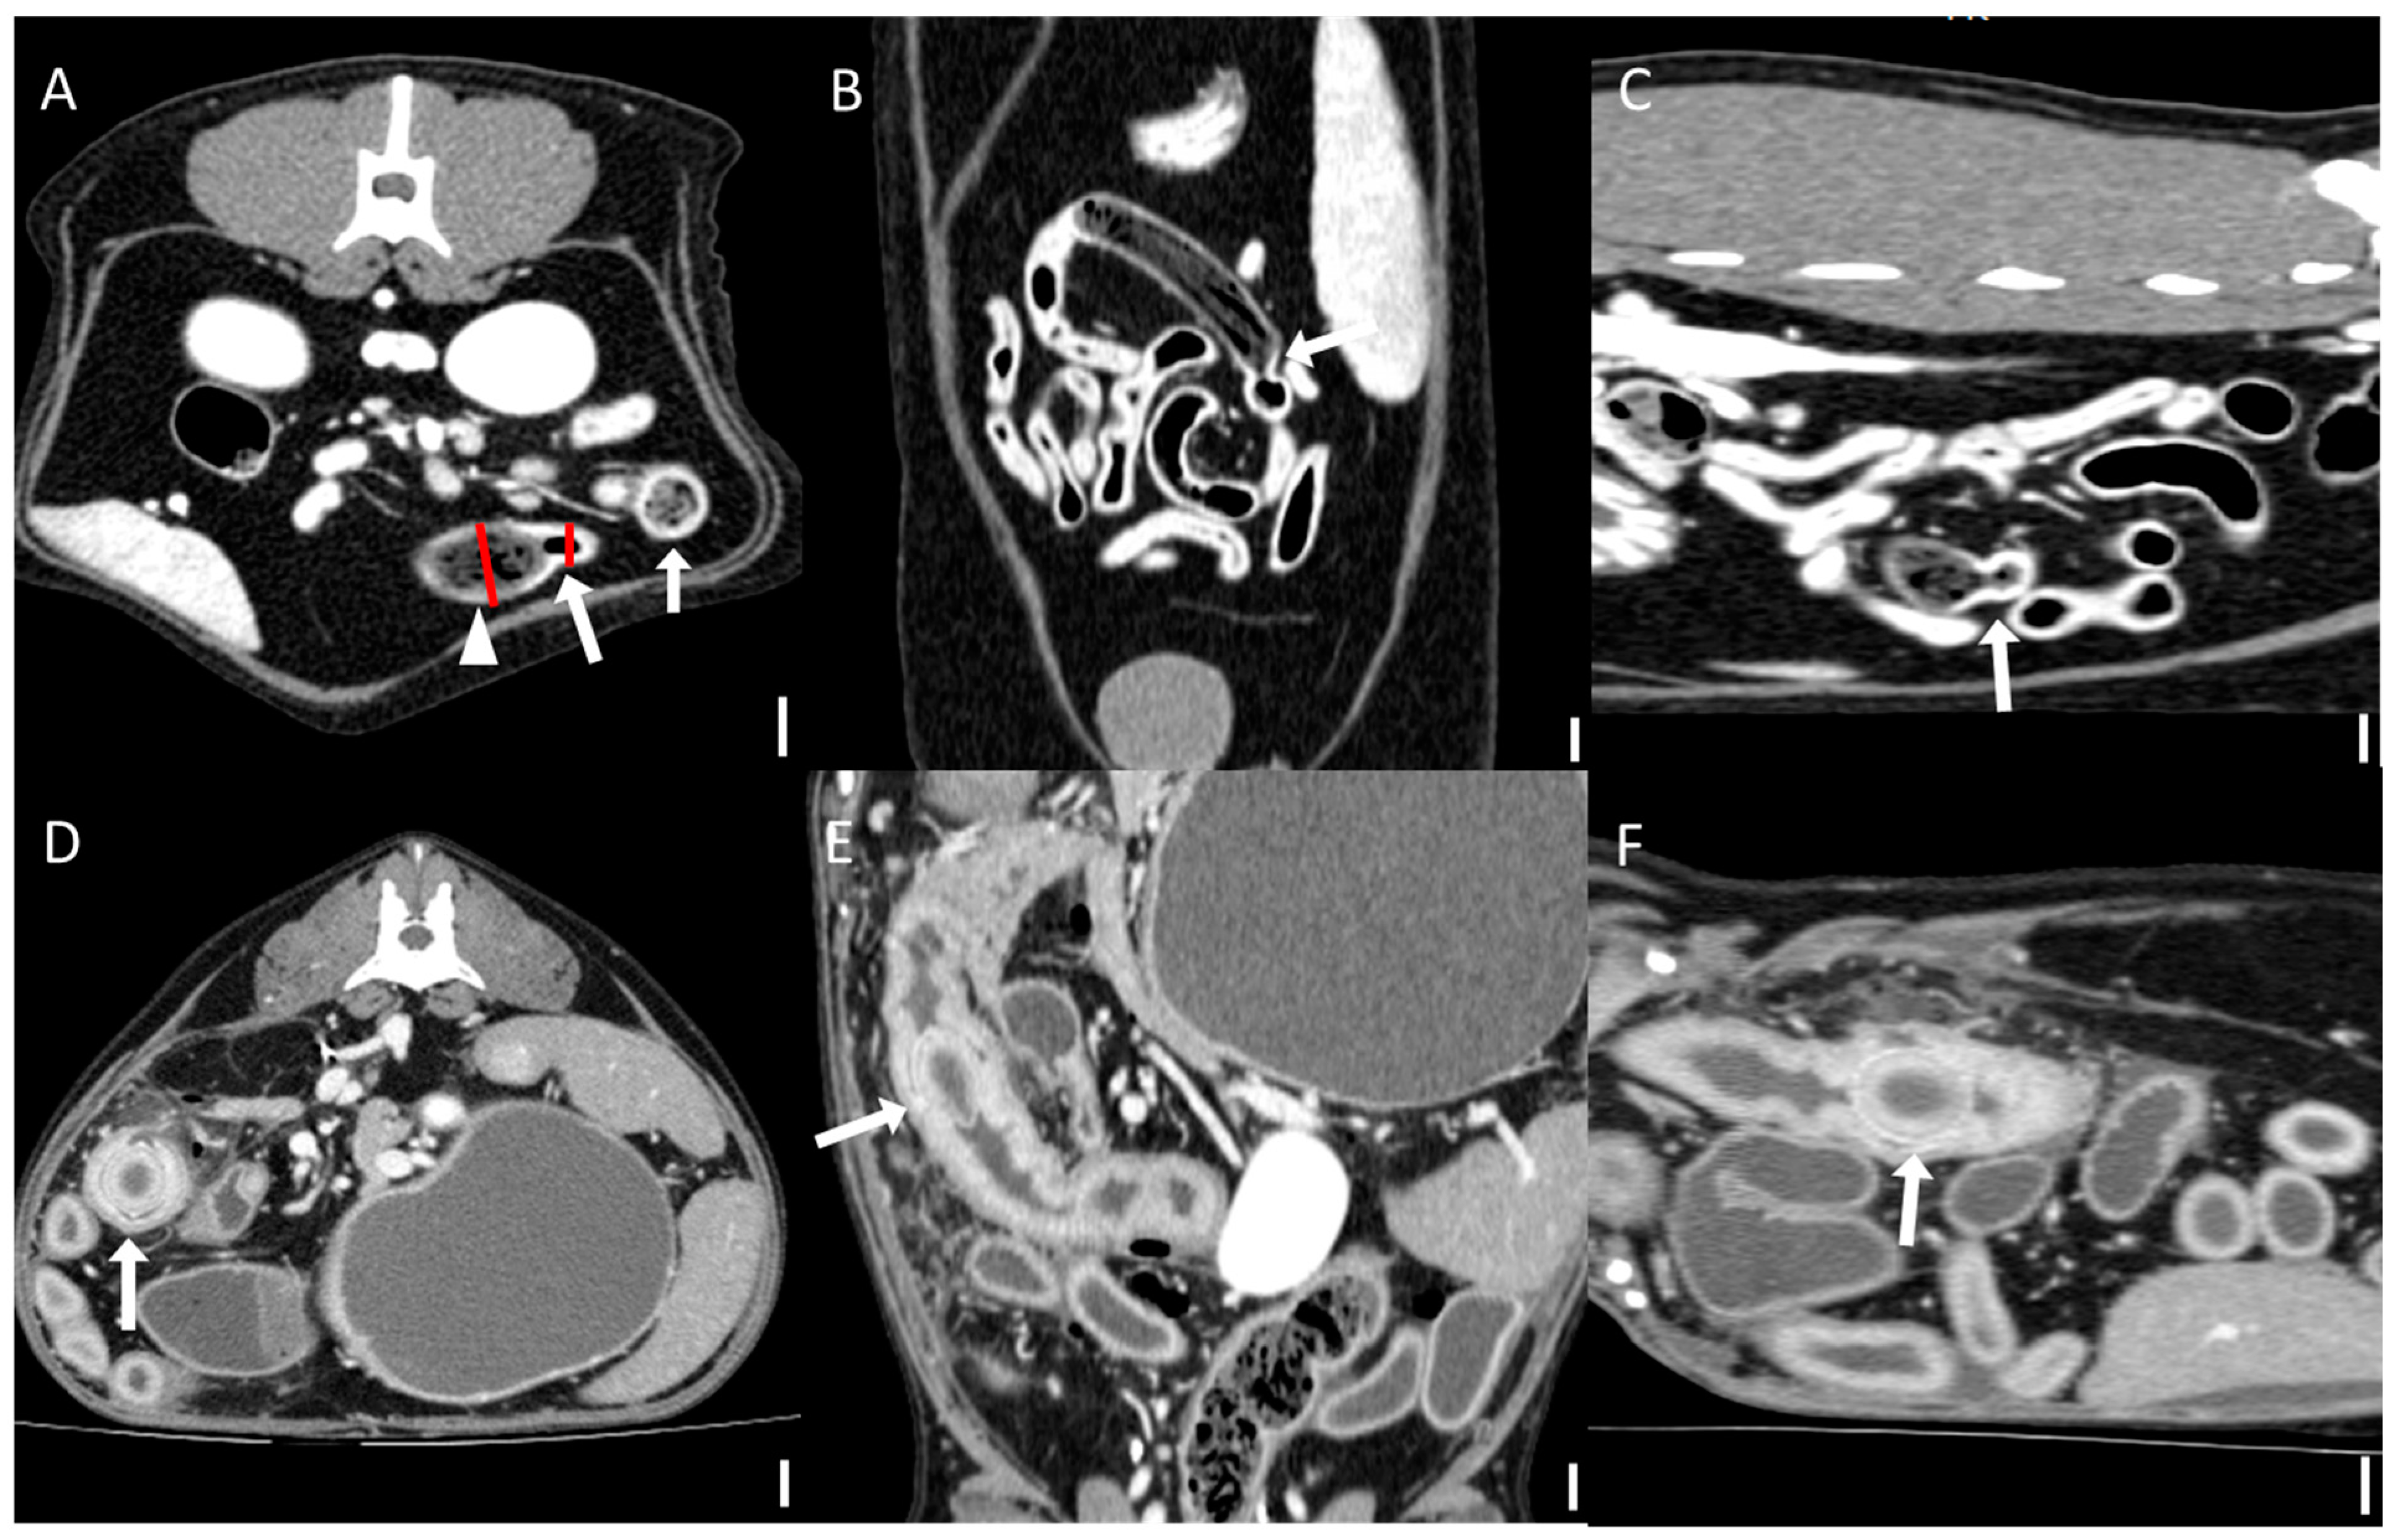

Computed tomography (CT) images were evaluated using multiplanar reconstruction tools provided by Radiant software. In most cases, postcontrast images were available; however, precontrast images were used specifically for attenuation value (HU) measurements of foreign bodies. CT evaluations included both qualitative and quantitative assessments. Qualitative CT criteria included the presence of a transition zone, defined as an area where the bowel abruptly changes from dilated to normal; collapsed segments [18] (Figure 1); the identification of the boundary between foreign bodies and intestinal contents; and the location of the foreign bodies. Gastric foreign bodies were excluded from transition zone evaluation, as the stomach does not exhibit a discrete diameter change consistent with the transition zone definition, which applies specifically to small bowel obstruction [19]. The presence of a boundary between the foreign body and the small intestinal contents was also evaluated through multiplanar reconstruction. The location of foreign bodies was categorized as follows: stomach, duodenum (the portion of the intestine extending aborally from the stomach to the proximal jejunum situated to the left of the mesenteric root), jejunum (the section of intestine between the aborad broad portion of the duodenum and ileum), ileum (the distal portion of the small intestine located abroad to ileocolic junction), and multisegmental involvement [4]. The quantitative CT evaluation criteria included the mean, maximum, and minimum attenuation values of the foreign bodies; the ratio of the small intestinal diameter between the most distended segment proximal (orad) to the foreign body and the adjacent collapsed distal (aborad) segment [15], (Figure 1); the number of complications identified on CT imaging caused by foreign bodies; and the severity of small intestinal dilation caused by foreign bodies normalized to vertebral measurements (SI/L5 in dogs and SI/L2 endplate in cats). Attenuation value measurements were conducted on precontrast images, with values measured in Hounsfield units (HUs) within manually drawn circular regions of interest typically 15–20 mm2 in area (Figure 2). For distinct foreign bodies, ROIs were placed directly within the visible object. In cases of bezoars, measurements were taken from the area presumed to contain the foreign material, based on the site of obstruction identified on CT. ROIs were carefully positioned to avoid intraluminal gas or the adjacent intestinal wall, and three measurements were averaged for each case. Complications identified on CT imaging included signs of peritonitis (e.g., increased mesenteric density and peritoneal fluid) [20], rupture of the bowel wall, involvement of foreign bodies across multiple segments [21], foreign bodies affecting organs beyond the gastrointestinal tract (Figure 3), signs of bowel wall ischemia or hypoxic changes, and the degree of obstruction (complete or partial). The severity of small intestinal dilation was classified as normal (SI/L5 < 1.6 in dogs, SI/L2 < 2.0 in cats), mild (SI/L5 1.6–2.0 in dogs, SI/L2 2.0–2.5 in cats), moderate (SI/L5 2.0–2.4 in dogs, SI/L2 2.5–3.0 in cats), or severe (SI/L5 > 2.4 in dogs, SI/L2 > 3.0 in cats) [5,16,17,22]. This measurement was applied exclusively to small intestinal segments; gastric foreign bodies were excluded from this assessment.

Figure 1. Representative computed tomographic images of the transition zone and measurement of small intestinal diameter across transition zone (scale bar equals 1 cm). The presence of a transition zone and measurements of small intestinal diameter were evaluated by multiplanar reconstruction. (AC) Multiplanar CT images ((A): transverse, (B): dorsal, (C): sagittal) from a case of jejunal obstruction caused by trichobezoars in the jejunum (arrowhead). An abrupt change in intestinal diameter (arrow) can be seen, indicative of a transition zone. The small intestinal diameter was measured at the most distended segment proximal (orad) to the foreign body and at the adjacent collapsed distal (aborad) segment. Red lines indicate the measurement sites used to calculate the diameter ratio. (DF). CT images ((D): transverse, (E): dorsal, (F): sagittal) from a case of a duodenal foreign body, identified as a fruit pit (arrow), without a visible transition zone.